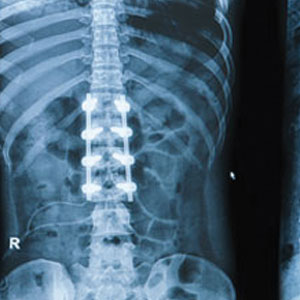

• Spinal fusion: Joining 2 vertebra with bone graft.